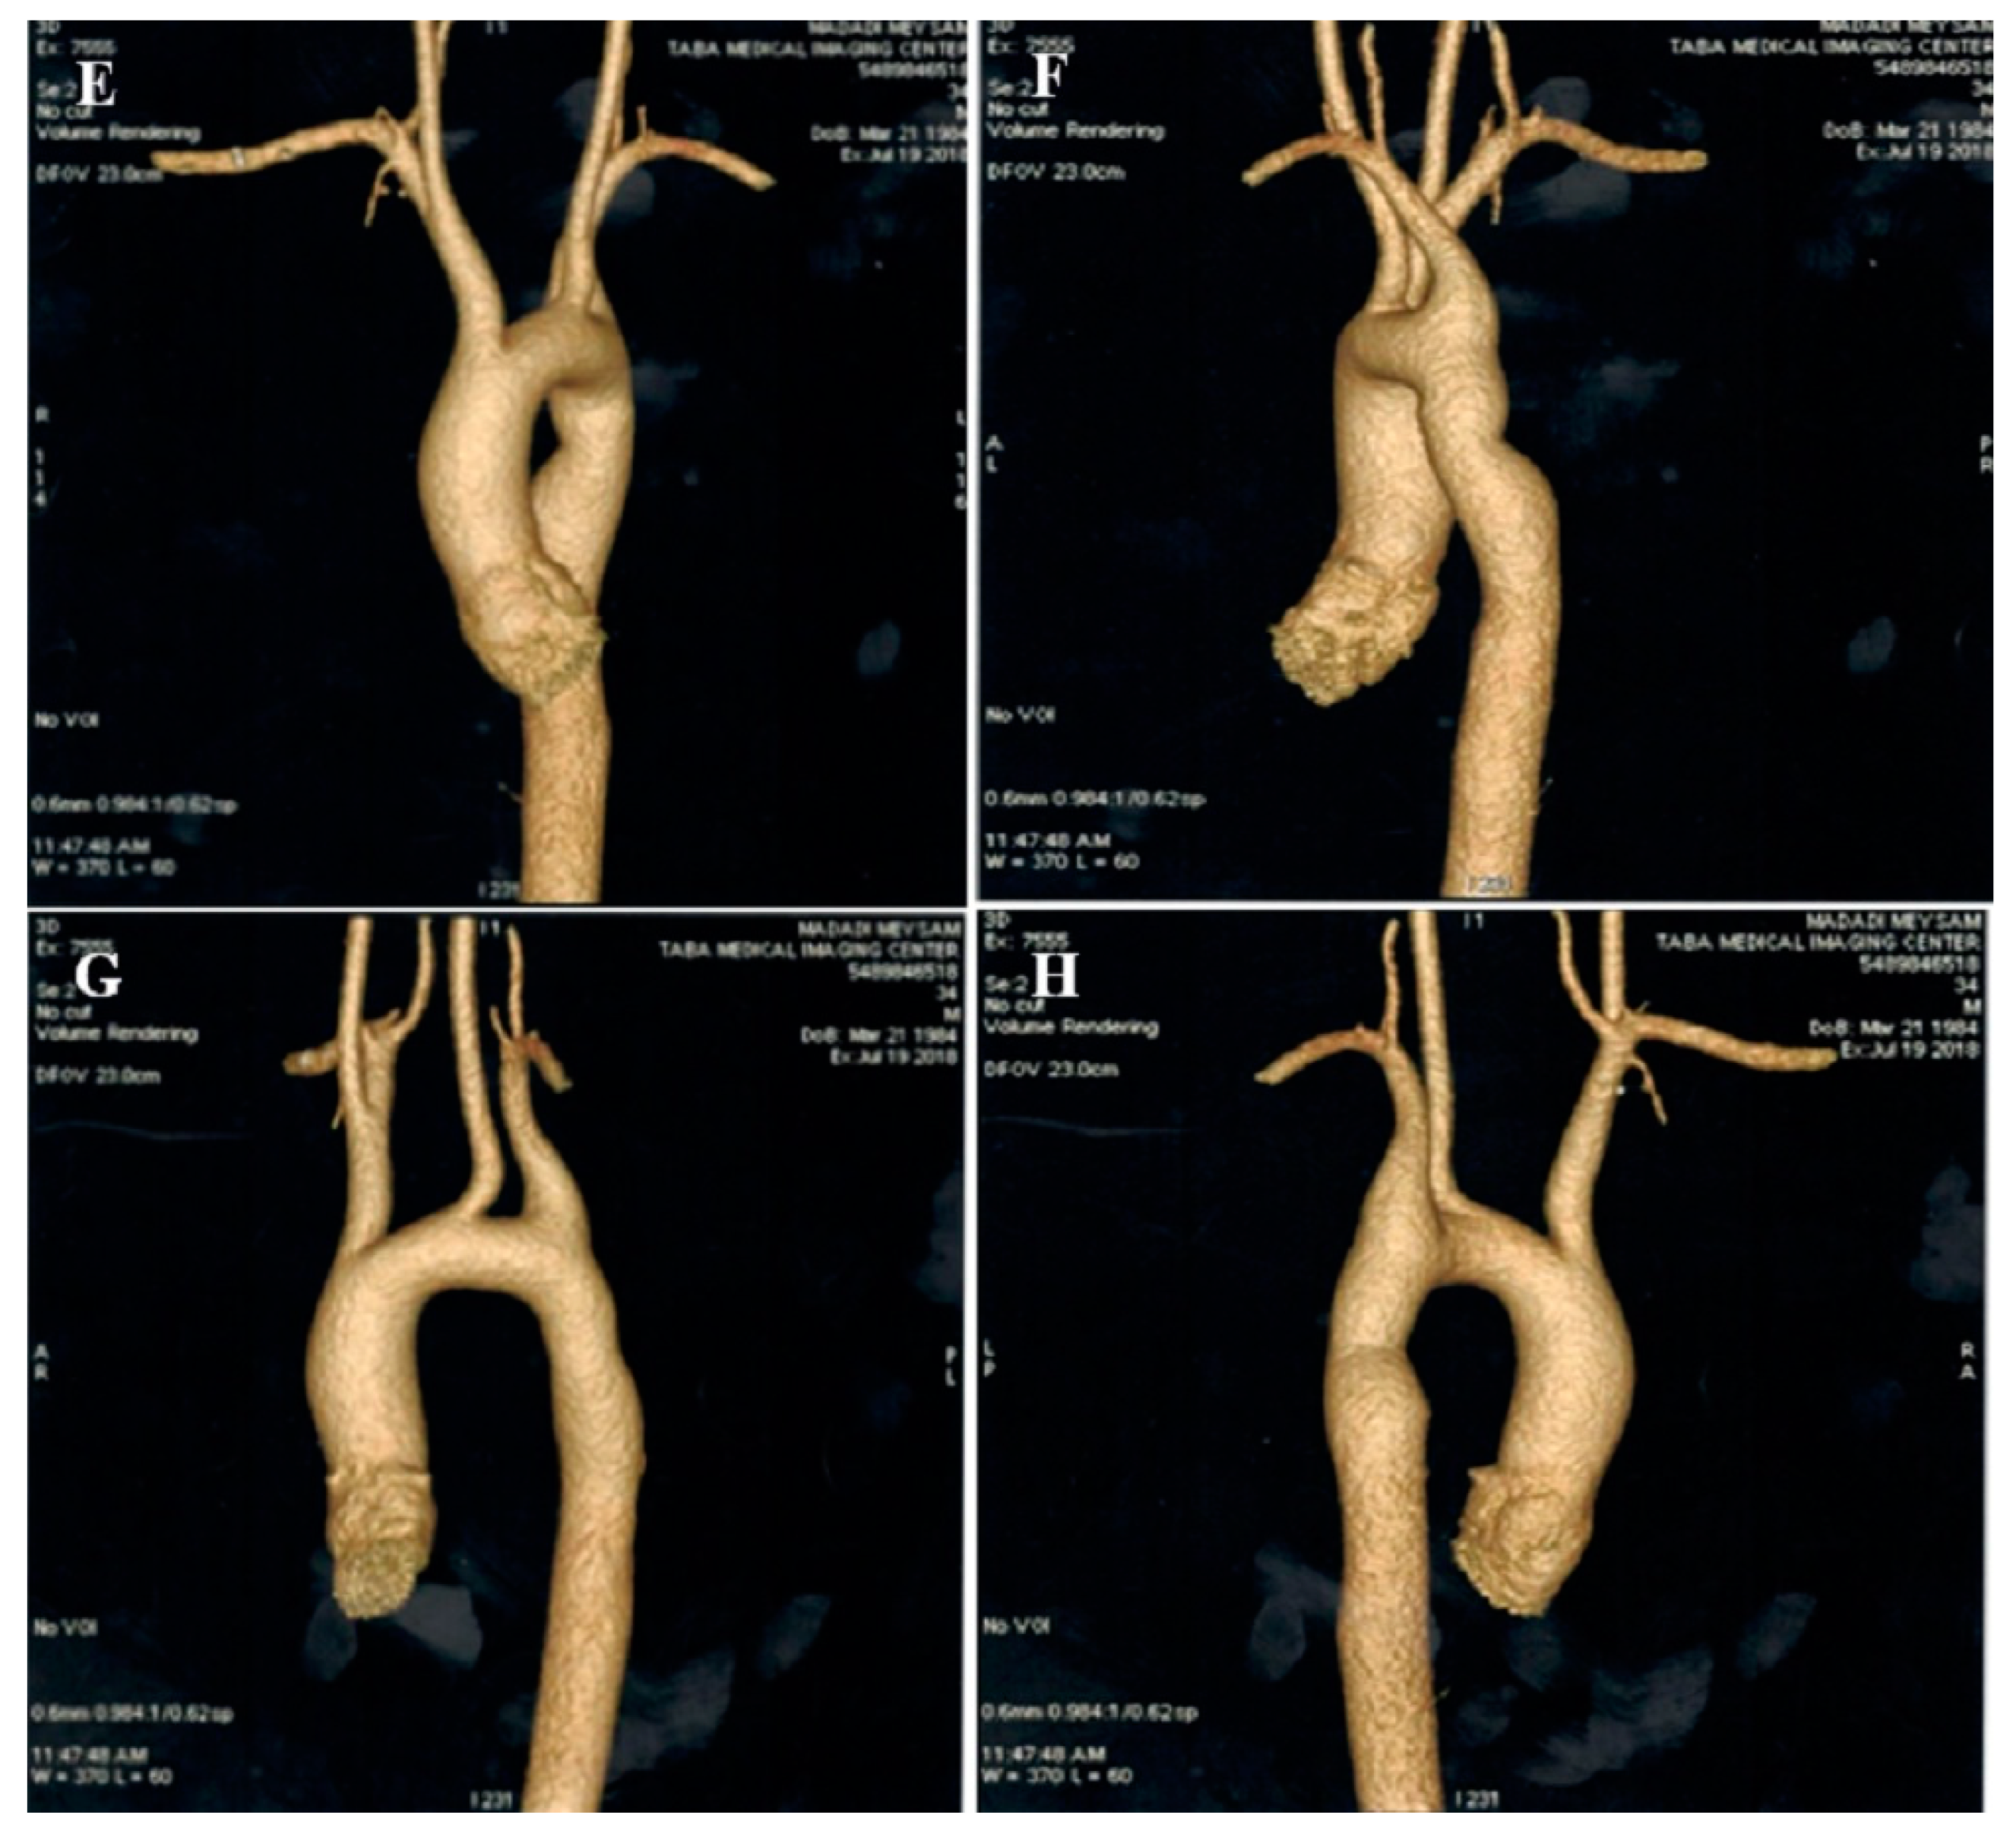

2.7. Case #7. BVNC, BAV, AS, and Dilated Aorta Ascending Aorta

A 48-year-old gentleman, a medical staffer, was referred to our clinic with dyspnea on moderate exercise and easy fatigability for 6 months, which had become worse over time. On cardiac auscultation, left- and right-sided S4 and S3 gallops, in addition to ejection systolic murmur grade III/VI in the aortic area, were audible. TTE showed non-compaction left and right ventricles with preserved biventricular systolic function, BAV, moderate AS, and dilated ascending aorta (diameter = 47 mm; indexed = 25 mm). At his request, he underwent diagnostic coronary angiography and left/right ventricular cineangiography, and the results showed patent epicardial coronaries plus hypertrabeculation of both ventricles in the biventricular cineangiography (Figure 7). A genetic study showed mutations in the MYH7 and MYBPC3 genes. The patient and the family members refused the genetic study because of the high costs of the test (not covered by the insurance). He denied undergoing CMR, due to claustrophobia, and was followed up medically (daily spironolactone 25 mg and carvedilol 6.25 mg twice per day). He was off pills 2 months later and did not return for further follow-up.

Figure 7.

Two-dimensional transthoracic echocardiographic views of case #7. (A,B); Biventricular non-compaction in apical four and three-chamber views. (C–F); Transesophageal echocardiography views, illustrating biventricular non-compaction in apical regions in addition to a thick, bicuspid aortic valve with restricted cusps motion (C,D), dilated ascending aorta (E), and increased transvalvular gradient in deep gastric view with a peak velocity of 3 m/s, in favor of moderate aortic stenosis (F). (G); Full volume three-dimensional transthoracic echocardiography, showing bicuspid, thick, and stenotic aortic valve (AVA by MPR = 1.4 cm2).